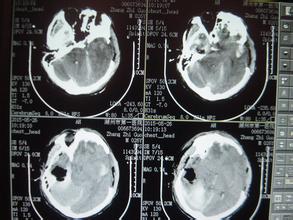

导读: 患者姓名:郭某某 性别:男 年龄:37岁 入院时间:2014年1月6日 病史:因头部坠落伤后昏迷,送院时急诊为重型开放型颅脑损伤,创伤性湿肺,左眼球贯通伤,左声带麻…

导读: 患者郑先生车祸后被紧急送入南京某医院,进行CT及相关影像检查后,发现脑干出血合并脑梗塞,经数次转院及治疗,苏醒后出院,后遗症有:右侧肢体偏瘫,语言、吞咽功能障碍,大…